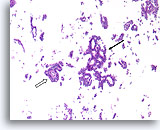

Atypische ductale hyperplasie, Borst FNA, Celblok.

Dit plaatje van de naaldspoeling van de patiënt in afbeelding 15 toont een uniforme populatie van vrijelijk stratificerende ductale cellen met een uniforme spreiding van kernen, afwezigheid van een stromingspatroon en de aanwezigheid van uniformere ronde ruimten in het kleinere fragment.

Atypische ductale hyperplasie, Borst FNA, Celblok.

Dit plaatje van de naaldspoeling van de patiënt in afbeelding 15 toont een uniforme populatie van vrijelijk stratificerende ductale cellen met een uniforme spreiding van kernen, afwezigheid van een stromingspatroon en de aanwezigheid van uniformere ronde ruimten in het kleinere fragment.

Atypische ductale hyperplasie, Borst FNA, Celblok.

Let op de gelijkvormigheid van de cellen (dit duidt op een afwezigheid van myoepitheliale cellen) en de uniforme spreiding van cellen zonder gedeelde polariteit.

Atypische ductale hyperplasie, Borst FNA, Celblok.

Let op de gelijkvormigheid van de cellen (dit duidt op een afwezigheid van myoepitheliale cellen) en de uniforme spreiding van cellen zonder gedeelde polariteit.